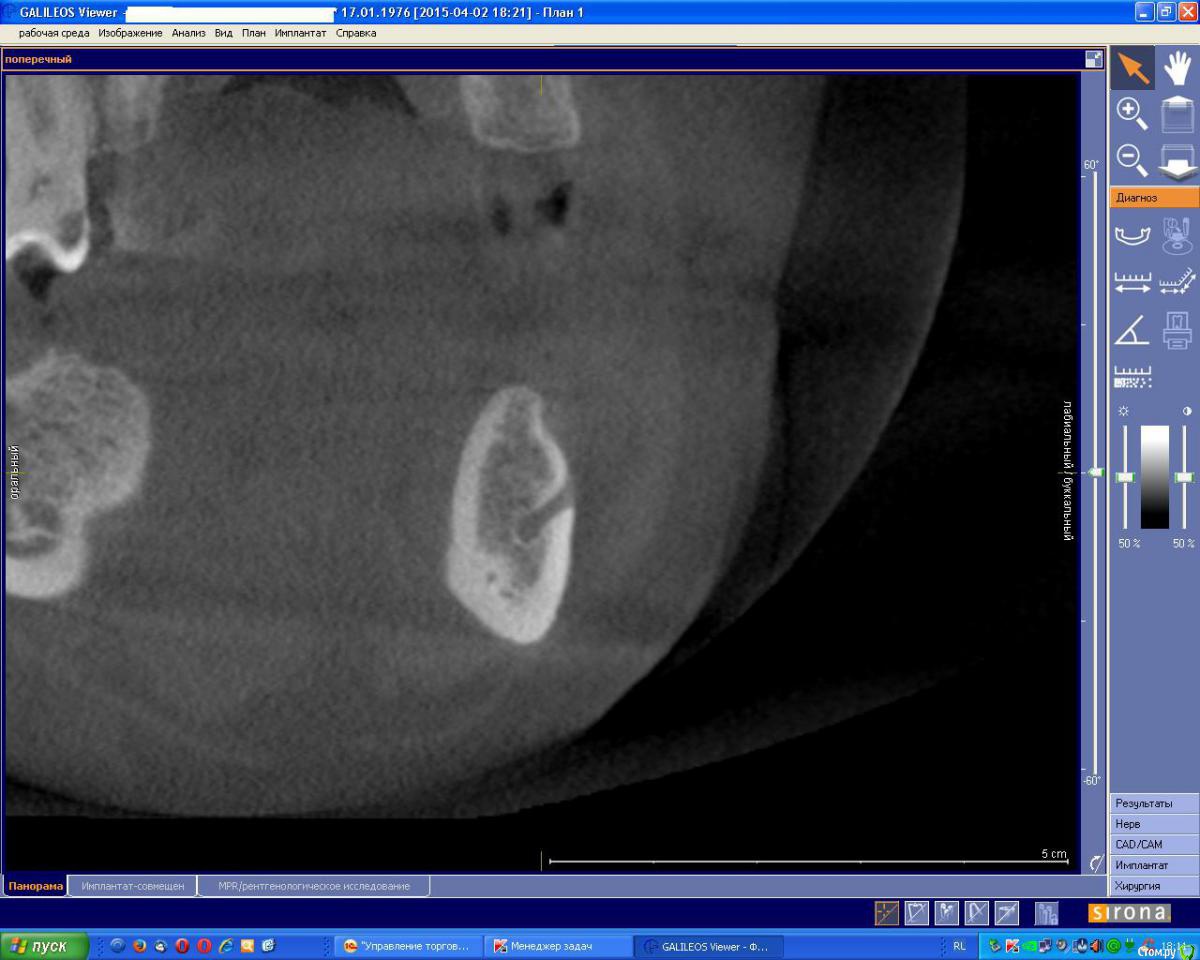

an_ver Опубликовано 4 мая, 2015 Поделиться Опубликовано 4 мая, 2015 На первом снимке мент.отверстие,на втором артерия? Доп.отверстие ментальное? Ссылка на комментарий

Alexey Doc Опубликовано 4 мая, 2015 Поделиться Опубликовано 4 мая, 2015 Думаю что да.нижнечелюстной канал иногда открывается не одним отверстием. Или Просто какая то нерегулярная артерия 1 Ссылка на комментарий

natan. Опубликовано 21 мая, 2015 Поделиться Опубликовано 21 мая, 2015 здравствуйте ,это incisive canal иннервирует передние зубы.он вам не мешает Ссылка на комментарий

Kazankov.Egor Опубликовано 23 мая, 2015 Поделиться Опубликовано 23 мая, 2015 Предположу))) начнем считать зубки7-6(корень)-5(лунка)- канал подбородочного нерва?) Ссылка на комментарий